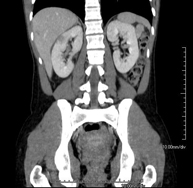

- Abdomen y pelvis- TC Abdomen Prueba diagnóstica que consiste en obtener imágenes del abdomen de alta definición anatómica (hígado, vesícula biliar, vía biliar, páncreas, bazo, estómago, intestinos, riñones, estructuras vasculares, vejiga, útero y ovarios, etc.) mediante el empleo de un equipo de TC (Tomografía Computarizada). Dichas imágenes se estudian posteriormente en una estación de trabajo que permite reconstrucciones bidimensionales en diferentes planos del espacio, y también reconstrucciones 3D (volumétricas). La mayoría de estudios requieren el empleo de contraste yodado para mejorar la definición de las imágenes. Prueba diagnóstica que consiste en obtener imágenes del abdomen de alta definición anatómica (hígado, vesícula biliar, vía biliar, páncreas, bazo, estómago, intestinos, riñones, estructuras vasculares, vejiga, útero y ovarios, etc.) mediante el empleo de un equipo de TC (Tomografía Computarizada). Dichas imágenes se estudian posteriormente en una estación de trabajo que permite reconstrucciones bidimensionales en diferentes planos del espacio, y también reconstrucciones 3D (volumétricas). La mayoría de estudios requieren el empleo de contraste yodado para mejorar la definición de las imágenes.

- TC Riñones Prueba diagnóstica que consiste en obtener imágenes bi y tridimensionales del riñón y del sistema urinario de alta definición anatómica mediante el empleo de un equipo de TC (Tomografía Computarizada). Se realiza el estudio antes y después del empleo de contraste yodado en diferentes "fases renales" para una valoración funcional y anatómica (parénquima renal, uréteres, vejiga urinaria, arterias y venas renales, etc.), así como las estructuras adyacentes (vena cava inferior, aorta abdominal, hígado, bazo, etc.). Está especialmente indicado ante la sospecha de lesiones renales, en pacientes con sangre en orina o hematuria, etc. Prueba diagnóstica que consiste en obtener imágenes bi y tridimensionales del riñón y del sistema urinario de alta definición anatómica mediante el empleo de un equipo de TC (Tomografía Computarizada). Se realiza el estudio antes y después del empleo de contraste yodado en diferentes "fases renales" para una valoración funcional y anatómica (parénquima renal, uréteres, vejiga urinaria, arterias y venas renales, etc.), así como las estructuras adyacentes (vena cava inferior, aorta abdominal, hígado, bazo, etc.). Está especialmente indicado ante la sospecha de lesiones renales, en pacientes con sangre en orina o hematuria, etc.